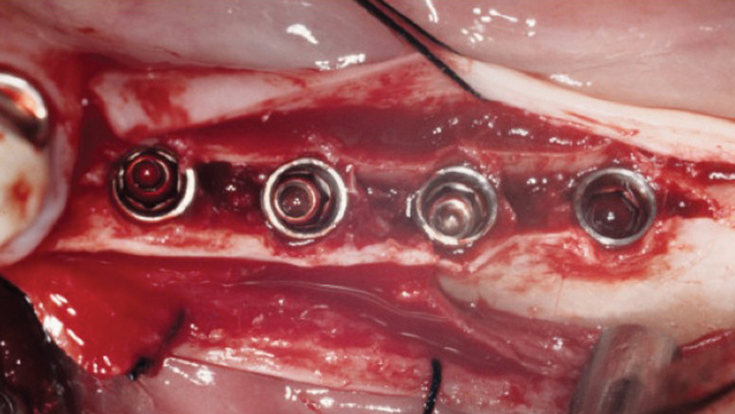

Clinical case: Installation of dental implants in complicated anatomic conditions using crest lifting methods

- Courtesy of Dr.Alexander Lysov, Russia -

Keywords

AnyRidge, complicated anatomic conditions, crest lift, MICA Kit, Dr. Alexander Lysov, bone regeneration, GBR, #26, maxillary posterior

Products:

AnyRidge implant system, MICA Kit

“Thin ridge expansion with minimally invasive surgery!

Use SmarThor & AnyRidge to place a wider diameter implant with minimal drilling after ridge splitting, even in thin ridge under 2mm! “